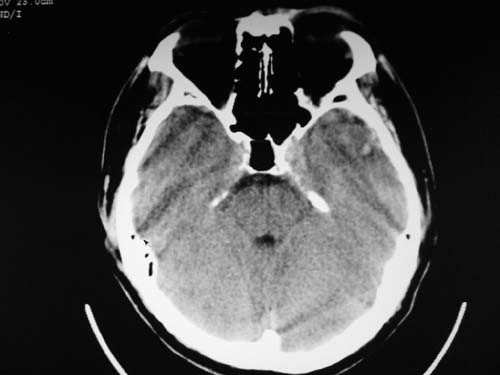

脑中线内血肿,是硬膜下的吗?

脑中线内血肿——硬膜下血肿。

脑中线内血肿——硬膜下血肿。我们一般认为中线即可是硬膜下,也可是蛛网膜下腔的。边缘锐利,张力高的考虑硬膜下的,边缘模糊的,考虑下腔的。如果有老师有肯定的答案,麻烦下给我发个短信

硬膜下血肿,有颅骨骨折

支持镰旁硬膜下血肿,颅骨骨折,头皮损伤.

这个病人年龄不小吧,右侧脑沟不清,中线结构稍有左移,右侧额颞顶及右镰旁硬膜下血肿,另有蛛血,骨折。

外伤后引起的颅骨骨折、硬膜下血肿、皮下血肿,颅骨骨折引起的矢状窦破裂,形成大脑纵裂内血肿。